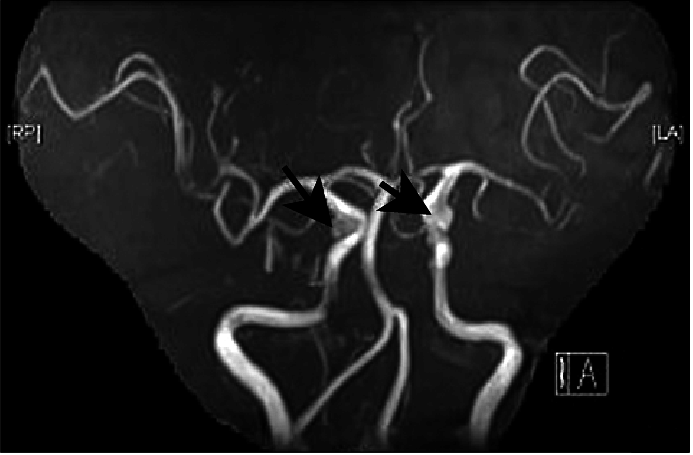

什么是后交通动脉瘤?后交通动脉瘤是常见的颅内动脉瘤之一,它是指发生于颈内动脉发出后交通动脉处的动脉瘤。据国外资料约占全部颅内动脉瘤的1/4,仅次于前交通动脉瘤而居二位,但国内资料统计其发生率处于。

后交通动脉瘤多发生于颈内动脉与后交通动脉交界处的远侧角,但亦可发生于后交通动脉与脉络膜前动脉之间的颈内动脉壁上, 还有少数(4. 6%)动脉瘤发生于后交通动脉本身,或后交通动脉发出点的近侧角处。